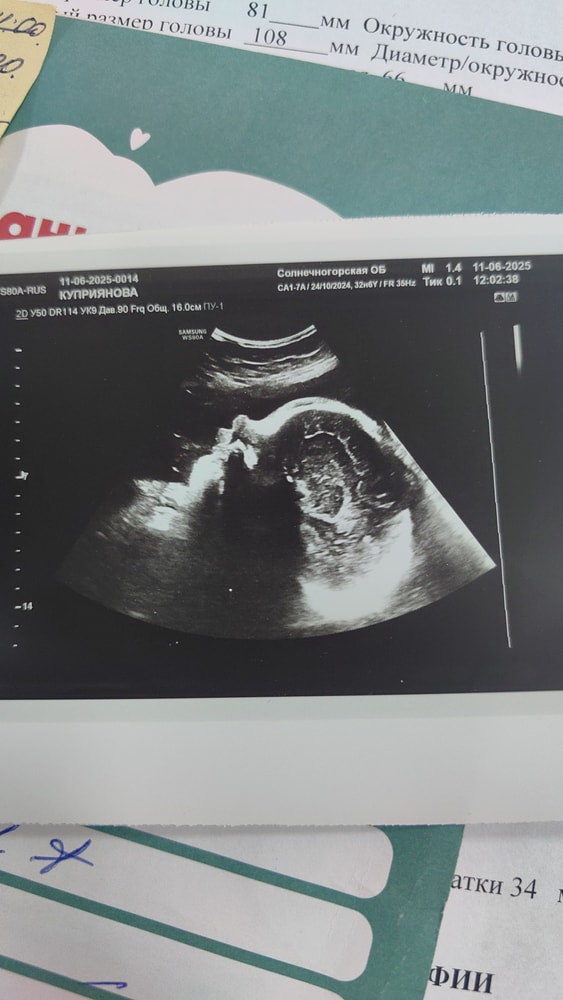

33 недели нам) ходила вчера на 3 скрининг. Вес 2.035кг из поперечного предлежания перевернулась на попу. Теперь мы сидим на попе. Назначили дополнительно узи на 36 недели. А так по показаниям все хорошо. Прибавка за 2 недели 900гр. Общая 5кг.